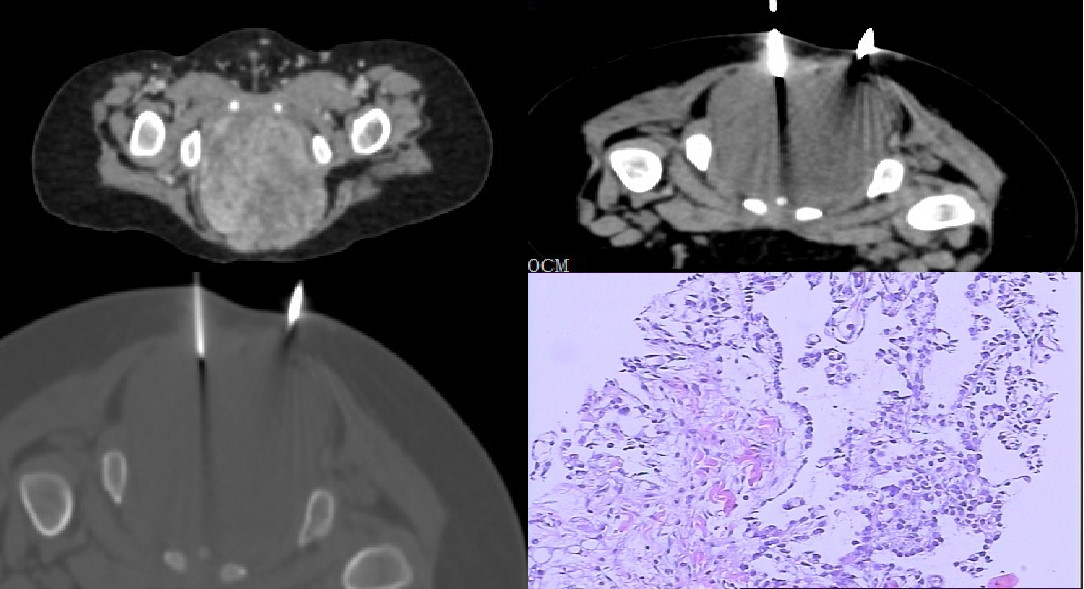

穿刺活检

穿刺活检是病理学检查的一个特殊类型。对包块进行组织学穿刺,取出组织后,进行病理学检查来明确诊断。